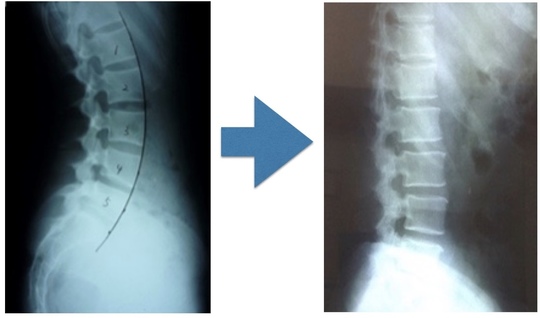

反っている腰椎の関節の動きを作り、反りを減らしていく事が次の課題になります。

腰が反っている状態からフラットにする必要があります。

腰椎の動きと骨盤の動きを作らなければ腰のそりは解消しませんし、筋・靭帯などたくさんの組織があります。

長い期間、腰がそっている方は関節の動きが制限されています

だから腰・骨盤の関節の動きを作らないといけません。